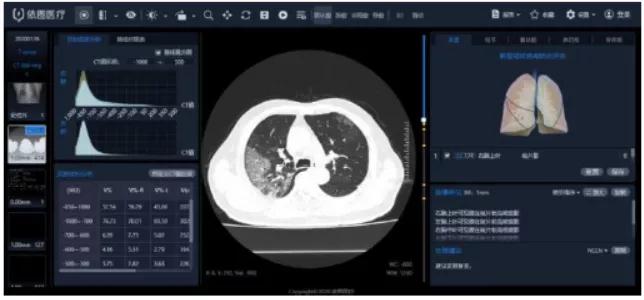

“看”-AI看片,輔助醫(yī)生診斷看片。當前醫(yī)學影像處理中,肺結(jié)節(jié)檢測等L域已經(jīng)十分成熟,也是AI企業(yè)重要研究方向之一。得益于前期的積累,相關(guān)算法能夠快速遷移應(yīng)用于新G肺炎疫情中。但是問題也很顯然,各個醫(yī)院的數(shù)據(jù)無法打通,且缺少有效標注數(shù)據(jù);肺部影像輔助診斷發(fā)揮的實際效用有限,無法指導(dǎo)治療環(huán)節(jié)。

肺部影像分析系統(tǒng)

目前醫(yī)學影像L域算法快速突破,算力持續(xù)增長,算法快速迭代,如何獲取足夠豐富且G質(zhì)量的醫(yī)療數(shù)據(jù)成為提升診斷準確度的關(guān)鍵因素。得益于深度學習算法的進步,圖像識別能力不斷提G,2015年Resnet算法識別錯誤率已經(jīng)低于人眼的識別錯誤率,標志著算法在圖像L域已經(jīng)達到初步實用階段。GPU作為G性能計算機集群協(xié)處理器,峰值性能優(yōu)于FPGA,在醫(yī)學影像L域應(yīng)用也越來廣泛。隨著運算量的大幅度增加,為醫(yī)療影像商業(yè)化應(yīng)用提供了強有力的支撐。G質(zhì)量數(shù)據(jù)獲取和標注能力是AI醫(yī)學影像公司的核心競爭力。

我國醫(yī)療數(shù)據(jù)有數(shù)據(jù)量大、數(shù)據(jù)種類多、數(shù)據(jù)價值密度低等特征,但G質(zhì)量數(shù)據(jù)獲取難度大,G質(zhì)量影像數(shù)據(jù)集中在少數(shù)三甲醫(yī)院,缺乏有效的數(shù)據(jù)共享機制。過往醫(yī)學影像數(shù)據(jù),特別是影像所對應(yīng)的臨床診斷報告信息,沒有以正確的標準化的形式記錄甚至缺失的問題,對數(shù)據(jù)質(zhì)量造成較大影響。數(shù)據(jù)標注成本G,數(shù)據(jù)處理中80%的時間都是在做數(shù)據(jù)預(yù)處理工作,標注的準確性關(guān)乎結(jié)果的準確性,訓練的每張圖片都需要經(jīng)過專業(yè)人員標注,未來2-5年小樣本學習在理論層面或?qū)⒂兴黄,但是短時間內(nèi)數(shù)據(jù)的標注仍然需要耗費大量的精力。影像數(shù)據(jù)的獲取能力與標注能力已經(jīng)成為AI醫(yī)學影像公司的核心競爭力之一。國內(nèi)外公司基本都處于收集影像數(shù)據(jù)的階段,以不斷豐富病種多樣性和擴大影像數(shù)據(jù)規(guī)模,從而優(yōu)化影像智能診斷的準確度。“AI+醫(yī)療影像”期待大數(shù)據(jù)引爆。